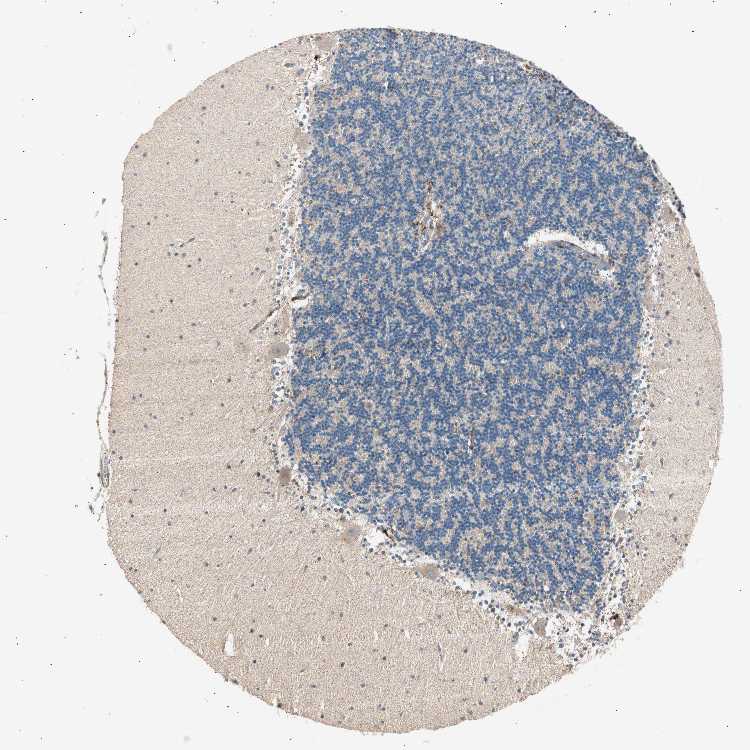

CEREBELLUM - Antibody stainingi

Antibody staining in the annotated cell types in the current human tissue is reported as not detected, low, medium, or high, based on conventional immunohistochemistry profiling in selected tissues. This score is based on the combination of the staining intensity and fraction of stained cells.

Each image is clickable and will lead to virtual microscopy that enables deeper exploration of all samples and also displays staining intensity scores, fraction scores and subcellular localization as well as patient and tissue information for each sample.

Antibody HPA006804

Purkinje cells Medium

Cells in granular layer Low

Cells in molecular layer Low